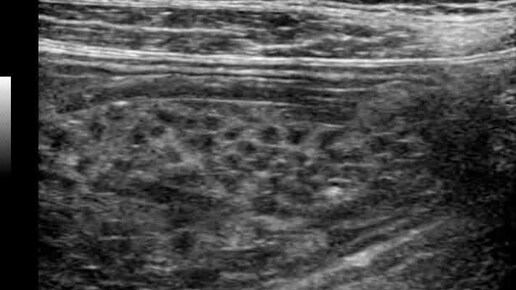

Спагетти в желудке. Видео к статье https://dzen.ru/a/ZwZGUaVaaQByJHfP

Ультразвуковые находки от врача УЗД Зорина Я.П.